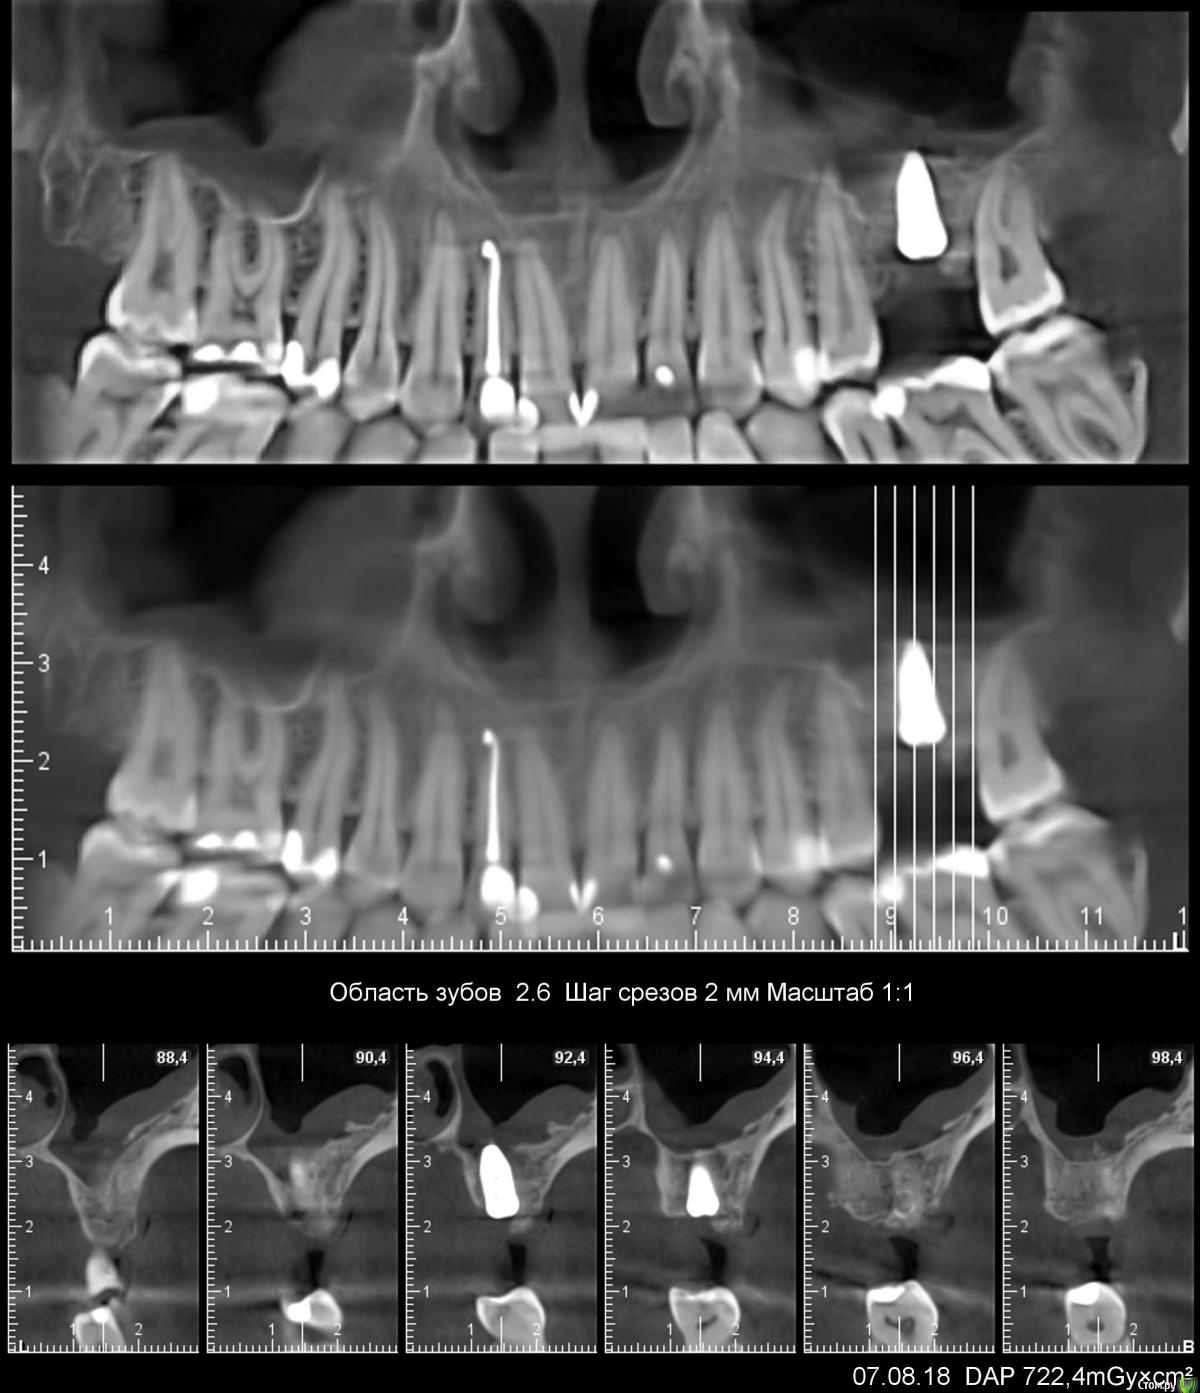

sole13 Опубликовано 26 апреля, 2018 Поделиться Опубликовано 26 апреля, 2018 посоветуйте, пожалуйста недавно удалили 26 зуб. КТ на дату 14 апреля (2, 5 месяца после удаления). Насколько я понимаю, в среднем у меня 6 мм кости. Возможен ли в моем случае закрытый синус лифтинг (а не открытый) и имплант 9 на 5 мм будет достаточен ?( высота и ширина) про достаточность - подразумевается, что конструкция будет выдерживать жевательную нагрузку на протяжении многих лет и при протезировании не будет "лошадиной" коронки. спасибо! Ссылка на комментарий

Irouil Опубликовано 2 мая, 2018 Поделиться Опубликовано 2 мая, 2018 (изменено) Коронка все равно выйдет большая, длинная вернее. Без костной пластики в сторону полости рта делать короткую коронку ненадёжно. По крайней мере по масштабам сделанных Вами срезов кажется именно так. Но я тоже согласен на 100, зуб боковой, эстетику не каждый стоматолог заметит при осмотре, с точки зрения надёжности и предсказуемости результатов синус лифт и имплантация. Да и запротезируетесь раньше. Изменено 2 мая, 2018 пользователем Irouil Ссылка на комментарий

sole13 Опубликовано 10 августа, 2018 Автор Поделиться Опубликовано 10 августа, 2018 (изменено) уважаемые хирурги, прошу ваш совет 3 месяца назад было сделана имплантация 26 зуба, закрытый синус,сделано повторное свежее КТ через 3 месяца у меня ощущение постоянного комка слизи в носоглотке с момента операции (иногда отплевывается часть и это оч густое содержимое). пила 2 курса синупреда, 2 месяца на море, 2 курса ринофлоимуцила прокапала. если чуть заболеваю, то слева ощущение тяжести в крыле носа как при гайморите. хирург говорит, что перфорации гайморовой нет и в 50% случаях это нормальная реакция гайморовой - выделять слизь, что через месяца 3-4 у меня это пройдет. действительно гайморова пазуха не перфорирована и ощущение слизи -норма? еще меня смущает черная область вверху импланта справа на снимке и черное под имплантом и справа по вертикали - что это? Изменено 10 августа, 2018 пользователем sole13 Ссылка на комментарий